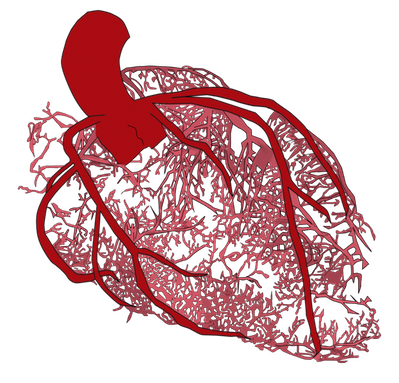

Angina is the name for the type of chest pain people feel when poor circulation starves their heart of blood. When describing what causes angina, doctors often compare the arteries of the heart to blocked pipes. We can think of “unclogging pipes” or “releasing a blockage” when we consider the treatment procedure: a stent. Sometimes people have angina, but their coronary arteries are not blocked. The analogy of a blocked pipe then stops making sense. This is not surprising, because the heart’s circulation is much more complicated than rigid metal pipes. Now the problem is somewhere else: in the tiny capillaries that dig into the heart muscle to feed it with blood.

To understand how Cardiac Syndrome X occurs, we need to take a short tour inside the heart muscle and peek at how its circulation works in broad terms. The arteries that feed blood to the heart are much more than rigid metal pipes. Arteries operate much like large organs in the body do: reacting to the environment and modifying their function as needed. When we exercise, the body’s demand for energy and oxygen goes up, so the heart starts pumping faster and stronger. When blood begins to rush through the arteries that feed blood to the heart, the walls of these arteries stretch. This stretching causes the release of substances that travel downstream, directing the small capillaries that penetrate the muscle to plump so they receive and deliver more blood. More blood being injected into the heart muscle allows it to squeeze stronger and faster. Microvascular dysfunction is a problem caused by a breakdown of this process. When a person suffering from Cardiac Syndrome X exercises, the capillaries that feed blood to the muscle do not work like they are supposed to. They do not plump to deliver more blood, so the heart muscle struggles without the blood supply it needs. This causes angina and shortness of breath. The mechanisms that cause the tiny blood vessels in the heart to plump when necessary are complex and incompletely understood. Still, several different things are well recognized to be related to the problem: